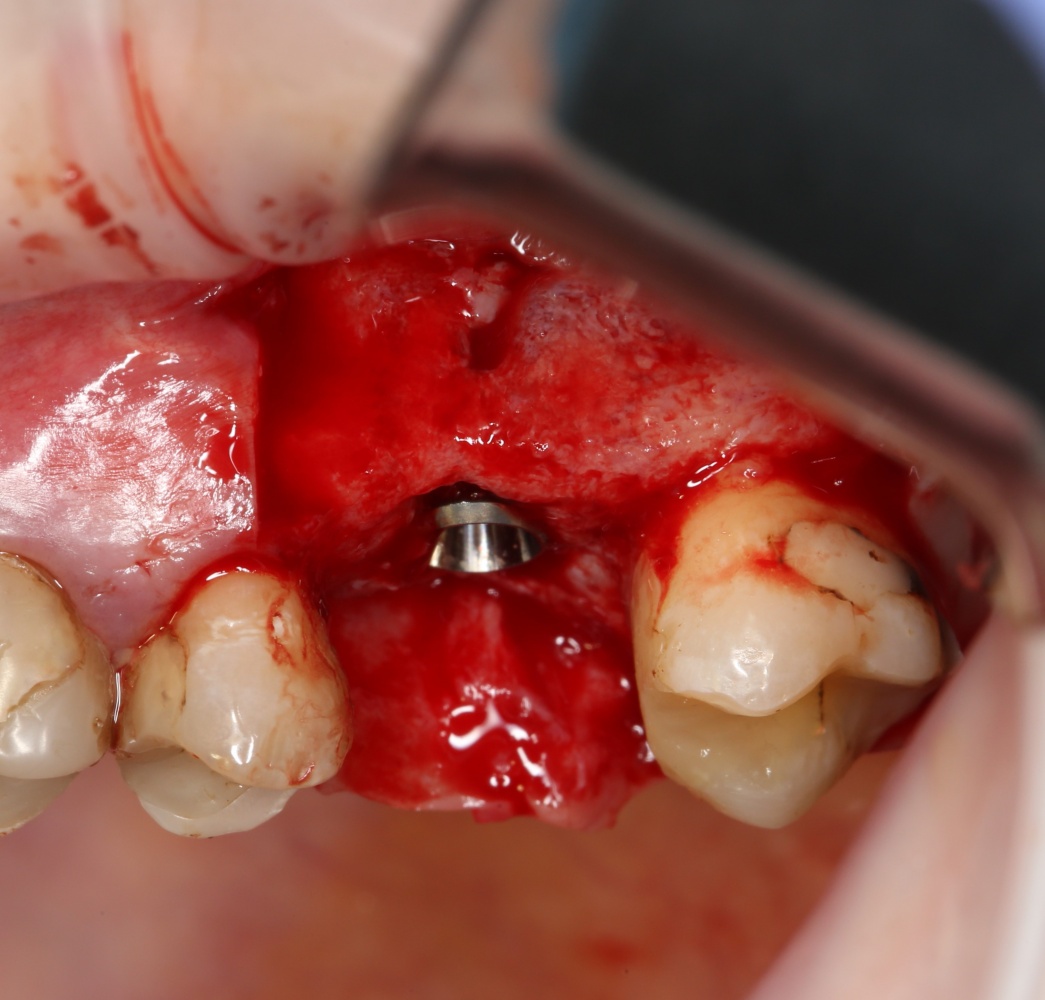

Простой синуслифтинг. Часть I.